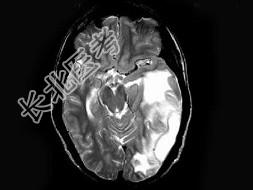

- 单项选择题男,30岁, 寒战,高热伴头痛, 呕吐10天,头颅MRI平扫及增强扫描见颅内不规则环形强化, 应诊断为 ( )

A、化脓性脑膜脑炎并脑脓肿形成

B、结核性脑膜脑炎并结核瘤形成

C、脑膜及颅内转移瘤

D、星形细胞瘤

E、未见异常